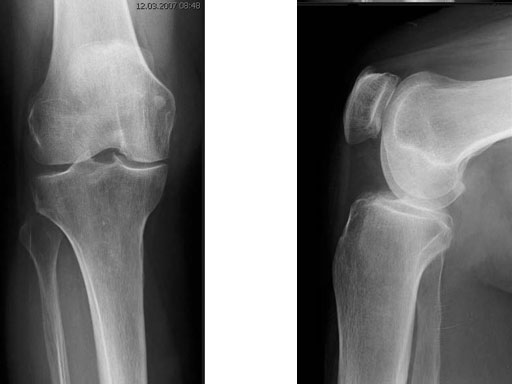

A 68-year-old female.

Case provided by Alex Staubli, Luzern, CH

The correction is planned on a long-leg standing x-ray. After surgery, the mechanical axis should pass through a point 63% on the lateral side of the total width of the tibial plateau in the frontal plane. A transverse or slightly oblique incision is used to avoid damage to the saphenous nerve. The distal fibers of the medial collateral ligament are detached from the tibia. Under fluoroscopic control, two wires are placed in the proximal tibia marking the transverse osteotomy plane. The cut usually starts at the upper margin of the pes anserinus and ends at the tip of the fibula on the lateral side. The wires are placed exactly parallel to the tibial plateau thus taking into consideration the individual tibial slope of the patient. An incomplete cut of the posterior two-thirds of the proximal tibia is performed with an oscillating saw guided by the wires. Continuous irrigation avoids burn injury to the bone. A second osteotomy is now performed in the anterior third of the tibia in an angle of 100 ending above the patellar tendon insertion. A smaller saw blade is used and the complete anterior cortex is cut exactly in the frontal plane. The osteotomy is now gradually opened by inserting flat chisels or a spreader-chisel into the posterior osteotomy cleft. This process may take some minutes and can usually be completed without fracture of the lateral cortex. A bone spreader is now placed in the posteromedial edge of the tibia and the chisels are removed. The leg is extended and the correction is checked with the fluoroscope. A long metal rod is placed between center of the hip joint and center of the ankle joint. The projection of this rod should be at the planned point of correction on the tibial plateau lateral of the midline. Eccentric collapse of the medial joint space may cause accidental overcorrection. In this case pressure on the foot may simulate loading and body weight. The correction can be fine-tuned by opening or closing the spreader. The TomoFix Medial Tibia Plate is now placed in a subcutaneous pocket. The implant is precontoured and usually fits well to the bone surface. The distance holders avoid compression of the medial collateral ligament and the pes anserinus. Three proximal bolts are placed near the subchondral sclerosis zone. The position of the bolts is adapted to the anatomy of the proximal tibia giving optimum purchase for the bolts. An oblique lag screw is inserted distal to the osteotomy. This screw in the first combination hole allows careful compression of the lateral osteotomy hinge and pretensioning of the implant. A stab incision is created on the shaft and the implant is fixed monocortically with bolts. The lag screw and the distance holders are replaced by bolts. The medial collateral ligament is released longitudinally to reduce medial compartment pressure and the wound is closed in layers. An overflow drain may be used. Clinical and experimental work has proven that when this technique is closely followed, corrections up to and over 15 mm can be performed without bone grafting or use of bone substitutes.